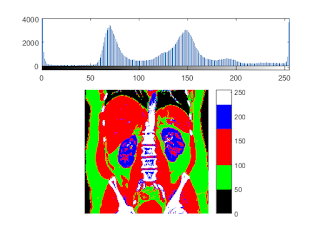

colormap( [repmat([0,0,0],[50,1]); ... % 0-50 repmat([0,1,0],[50,1]);... % 51-100 repmat([1,0,0],[75,1]);... % 100-175 repmat([0,0,1],[50,1]);... % 176-225 repmat([1,1,1],[56-25,1])]); colorbar

HSV space

convert to single-precision floating point

I = single(I); [ny,nx] = size(I); Ihsv = zeros(ny,nx,3); Ihsv(:,:,2) = 0.5; Ihsv(:,:,3) = I/max(I(:)); % add color th1 = 50; th2 = 100; th3 = 170; Ihsv(:,:,1) = Ihsv(:,:,1) + (I<th1) * 0; Ihsv(:,:,1) = Ihsv(:,:,1) + (I>th1 & I<th2) * 0.1; Ihsv(:,:,1) = Ihsv(:,:,1) + (I>th2 & I<th3) * 0.2; Ihsv(:,:,1) = Ihsv(:,:,1) + (I>th3 & I<225) * 0.5; Ihsv(:,:,1) = Ihsv(:,:,1) + (I>225) * 0.8; imshow(hsv2rgb(Ihsv));